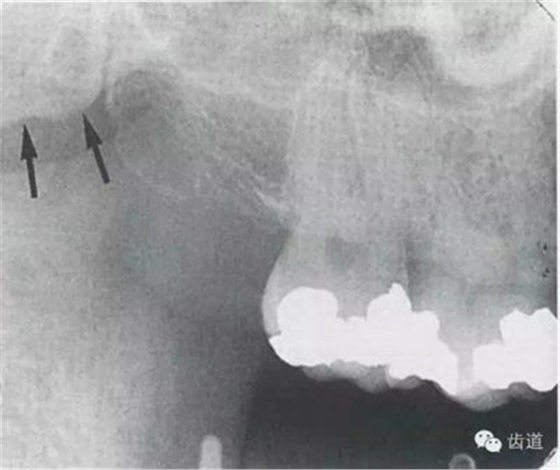

7)下頜角區(qū):

在下頜管的后下區(qū)域,骨小梁稀少,這是正常骨質(zhì)疏松區(qū)域 8)頦嵴: